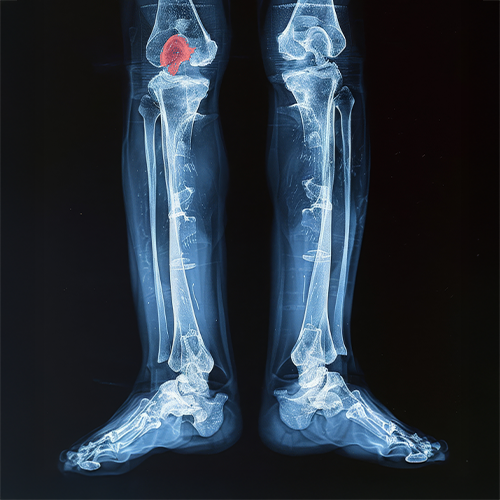

Skeletal & Joint Annotation

Landmark and region-level annotations on bones and joints support orthopedic analysis and sports medicine AI models.